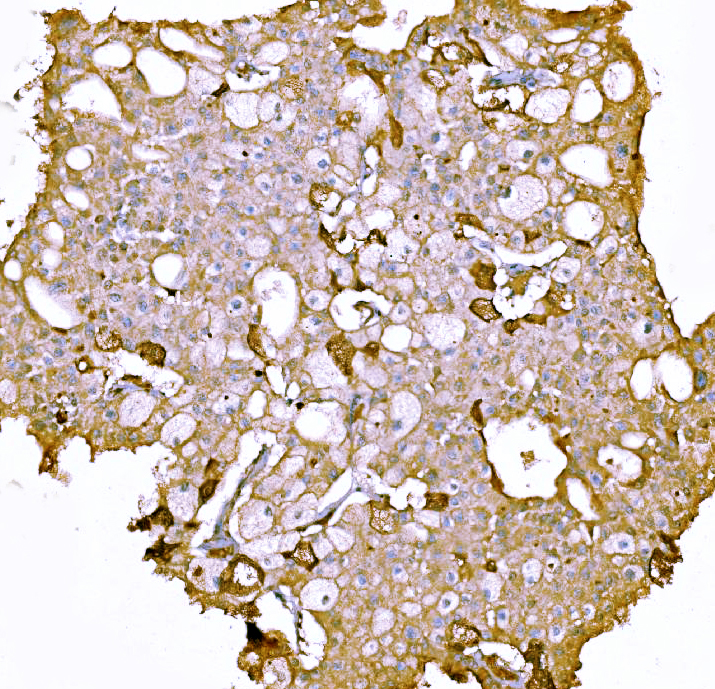

IHC analysis of F2 using anti-F2 antibody (M00044-2).

F2 was detected in a paraffin-embedded section of human liver cancer tissue. Biotinylated goat anti-mouse IgG was used as secondary antibody. The tissue section was incubated with mouse anti-F2 Antibody (M00044-2) at a dilution of 1:200 and developed using Strepavidin-Biotin-Complex (SABC) (Catalog # SA1021) with DAB (Catalog # AR1027) as the chromogen.